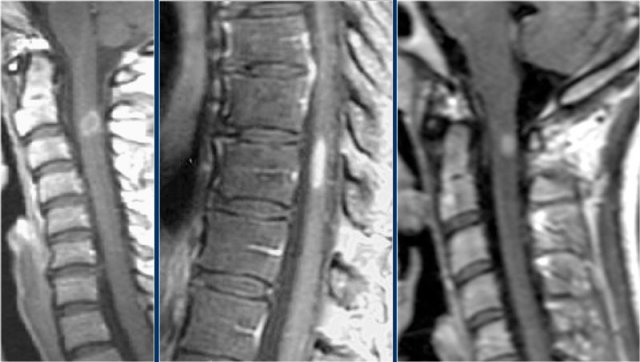

Here we have images of a typical case.

Many times the clinical history is very helpful like in this case.

This 24-year old patient had visual disturbances on one eye followed by weakness and sensory disturbances of the lower and upper extremities a couple of years later.

Now she presents with sensory disturbances of both lower extremities.

So we already think MS.

In the cord there are some well-defined lesions, but also some ill-defined foggy lesions.

The transverse image shows the dorsal location and the typical triangular shape.

Now what can we expect in the spinal cord of patients with MS.

It is like in the brain.

Frequently the lesions are focal like we see on the left image.

Less commonly there are diffuse abnormalities and then we have a tough differential diagnosis which will include TM and NMO.

On transverse images MS lesions typically have a round or triangular shape and are located posteriorly or laterally.

MS is the great mimicker and can also be located anteriorly like in this patient who has a lesion in the typical location (blue arrow) but also a lesion ventrally in the cord (red arrow).